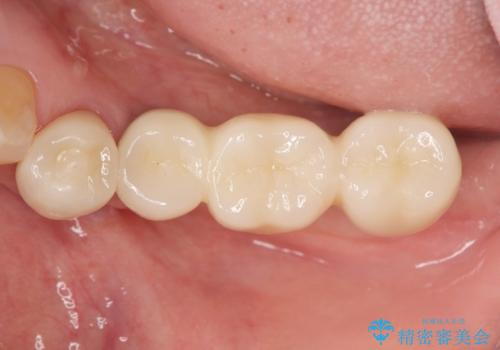

- 113.3万円(インプラント×2・チタンカスタムアバットメント×2・ジルコニアクラウン×3・仮歯×3)費用は治療当時の料金となります

長年使用してきた取り外しの必要な入れ歯と違い、しっかりと噛むことができ取り外しの必要のないインプラント治療で食事をより楽しめるようになりました。